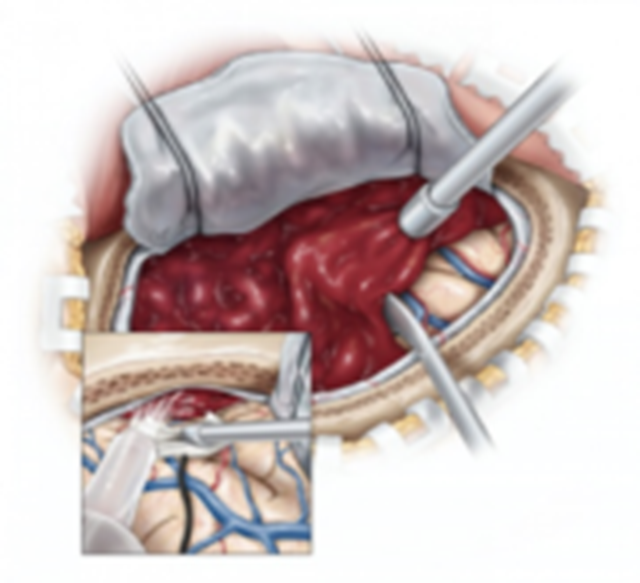

显微镜开颅手术

优点:

1.术野暴露好,可在短期内迅速清除血肿;

2.清除血肿止血充分,可缓解脑水肿和改善脑脊液循环通路,降压效果好。

缺点:

1.神经损伤;

2.二次出血的发生率高;

3.脑组织(尤其是深部脑组织)损伤大。